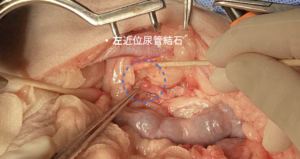

• 左側:近位尿管切開術により結石を摘出